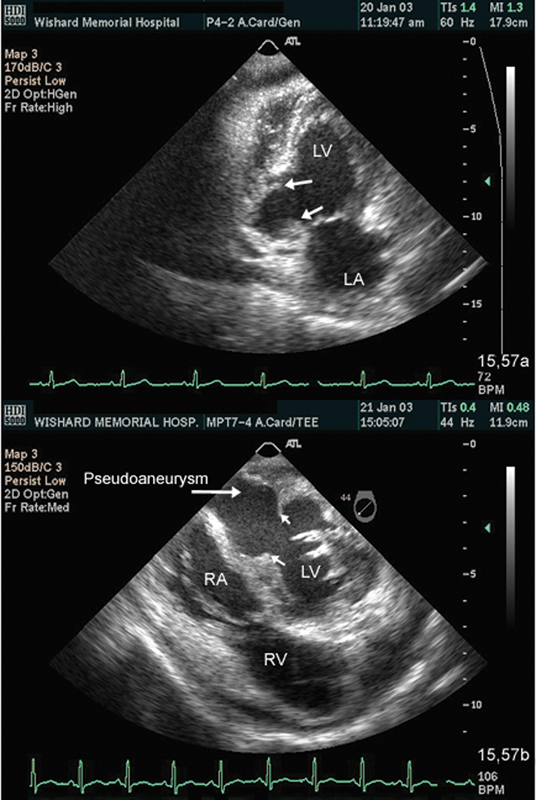

فحوصات تشخيصية لبعض امراض القلب والشرايين التاجية